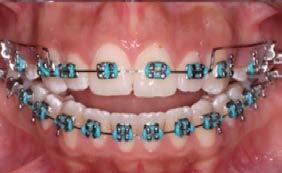

Caso clínico: paciente femenino de 19 años, patrón dolicofacial, perfil convexo, clase II esqueletal debido a una retrusión mandibular, mordida abierta anterior esqueletal, clase II molar, clase canina no establecida por mordida abierta, apiñamiento severo superior e inferior y deglución atípica.

Resultados: obtención de una clase canina I y clase molar II funcional, se corrigieron las sobremordidas horizontal y vertical, y se logró la coincidencia de líneas medias facial y dental. El manejo de la mordida abierta anterior se llevó a cabo por medio de la corrección del hábito de deglución atípica con la ayuda de spikes de resina, elásticos intermaxilares y arcos utility, y se obtuvieron buenos resultados estéticos, dentales y funcionales.